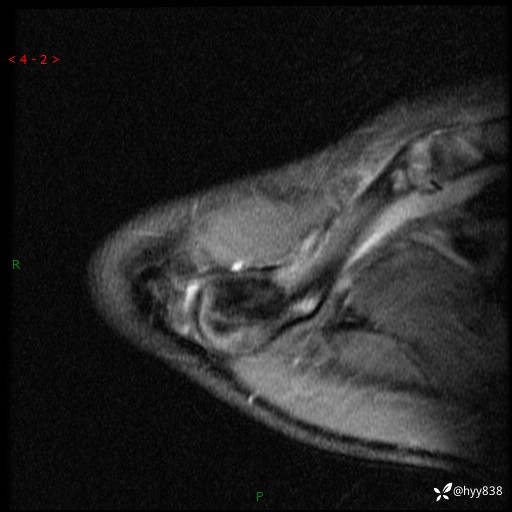

MRI(cor T1WI+T2WIfs+axi T2WIfs)